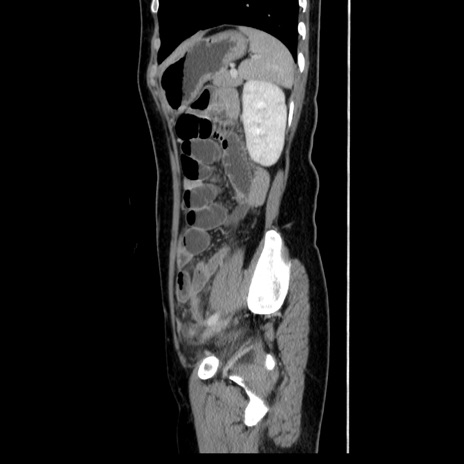

症例39(矢状断像)

【症例】40歳代女性

【主訴】上下腹部痛

【現病歴】2日目から下腹部痛あり。夜間は痛みで眠れなかった。昨日より上腹部痛と下痢が出現。臥位で痛みは軽快したため、休んでいた。本日になって臥位でも立位でも痛みが強くなってきたため救急要請。

【既往歴】子宮内膜症

【身体所見】部:平坦・軟、左上下腹部に圧痛あり、反跳痛あり。

【データ】WBC 21800、CRP 26.78

CT